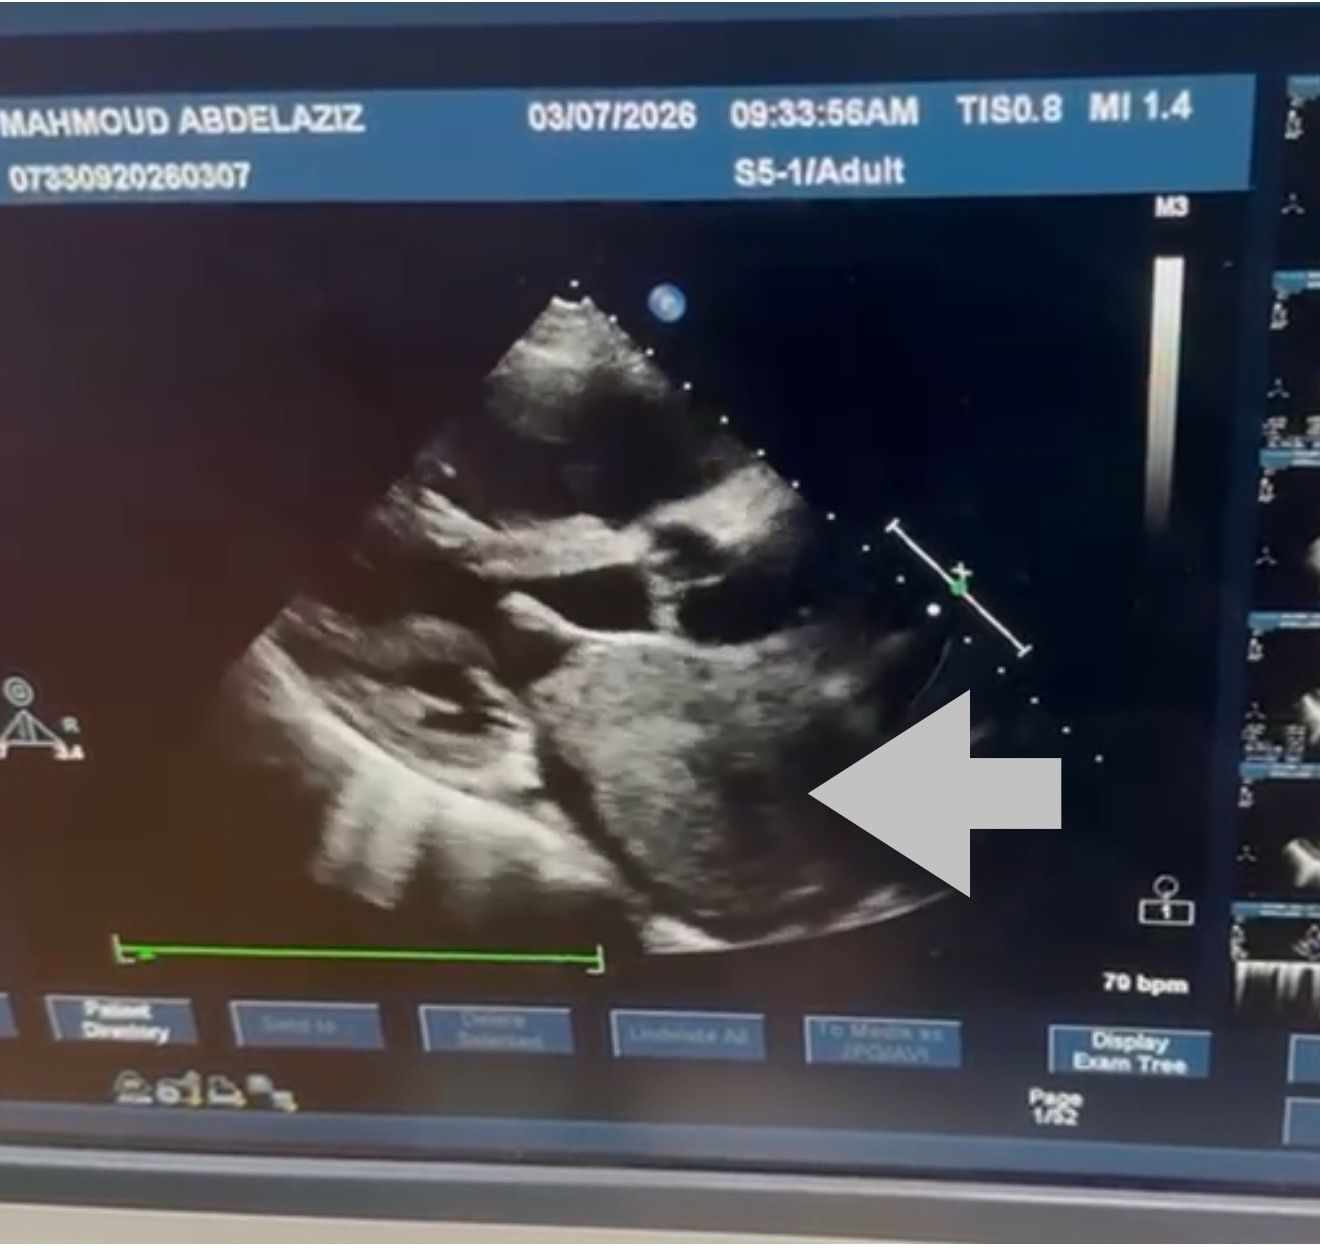

أعلنت مستشفيات قصر العيني، نجاح فريق جراحة القلب والصدر، في إجراء جراحة قلب معقدة لاستئصال ورم ضخم من داخل الأذين الأيسر لقلب مريض يبلغ من العمر 72 عامًا، بلغ حجمه نحو 10 × 8 سنتيمترات، وهو حجم نادر لمثل هذه الأورام القلبية.

وأوضح الفريق الطبي أن الورم من نوع Cardiac Myxoma، وهو من الأورام القلبية النادرة التي تنشأ داخل حجرات القلب، وقد تسبب في انسداد شديد بفتحة الصمام الميترالي أثناء تدفق الدم، ما أدى إلى ارتفاع ملحوظ في ضغط الشريان الرئوي، نتج عنه ارتجاع شديد بالصمام الثلاثي الشرفات، إضافة إلى تضخم بالأذين الأيسر وحدوث ذبذبة أذينية.

وخلال الجراحة التي استغرقت نحو أربع ساعات، تمكن الفريق الجراحي من استئصال الورم بالكامل مع قاعدته من الحاجز الأذيني، ثم إعادة ترميم الحاجز الأذيني باستخدام الغشاء التاموري، كما تم إجراء إصلاح جراحي للصمام الثلاثي الشرفات لعلاج الارتجاع الناتج عن ارتفاع ضغط الشريان الرئوي.